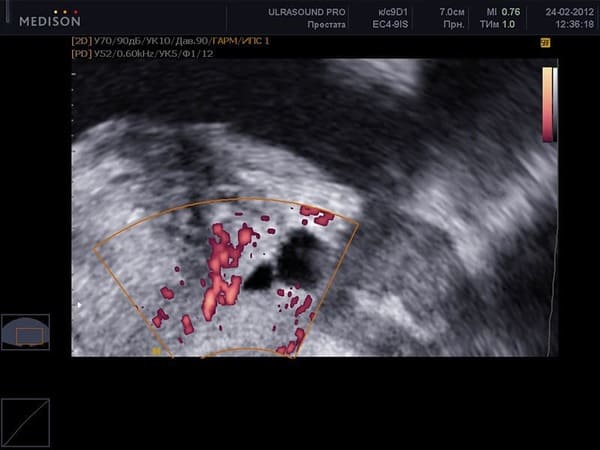

În absența sexului de calitate, alimentarea cu sânge a organelor pelviene dispare în timp. Problemele în stadiile incipiente sunt greu de detectat, iar atunci când sunt depistate, este necesară o intervenție chirurgicală. Vedeți fotografii de la Institutul de Urologie:

Cancer de prostată la un bărbat de 48 de ani.

Cancerul de prostată este cea mai frecventă cauză de deces (până la 88%) la bărbații care suferă de erecții slabe și lente. Acesta apare din cauza lipsei unei circulații sanguine adecvate în organele pelvine și a congestiei purulente în prostata însăși.